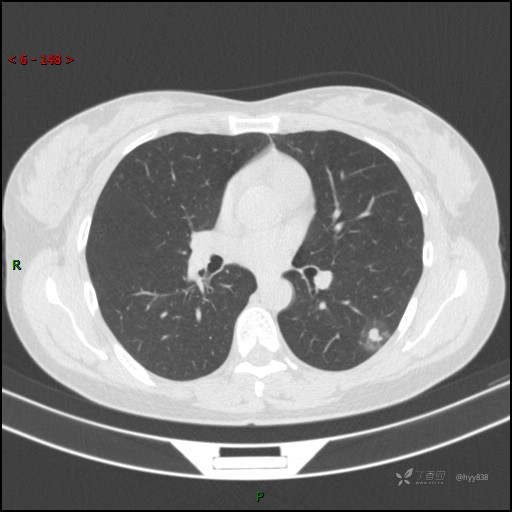

胸膜下“煎鸡蛋征”,感染 VS 炎症 VS 肿瘤,挑战有你---结果公布~

简要病史:干咳半月伴左胸部不适

辅助检查:CT

临床诊断:结节

讨论:病变性质?